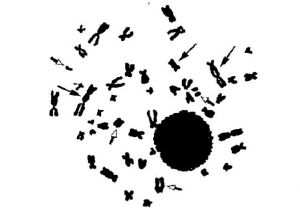

Ukázka chromozomových aberací, označeno šipkamí